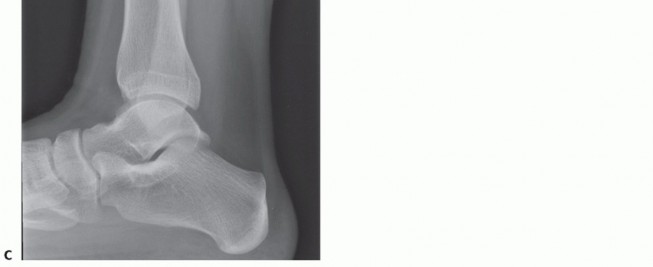

Plain radiographs

Obtain weight bearing, three views of the ankle Small OLTs may be missed.

Large OLTs are usually identified on plain radiographs (

FIG 1

).

Often limited in characterizing OLT because the two-dimensional study cannot define the three-dimensional OLT

Particularly useful in assessing lower leg, ankle, or foot malalignment that needs to be considered in the management of OLTs

May detect incidental OLTs (patient has a radiograph for a different problem and an OLT is incidentally identified on plain radiographs)

FIG 1 • Radiographs. A. AP radiograph of the ankle suggests symmetric alignment and a medial talar dome defect. B. Mortise view also suggests medial OLT. C. Lateral view shows anatomic alignment, with OLT less obvious.